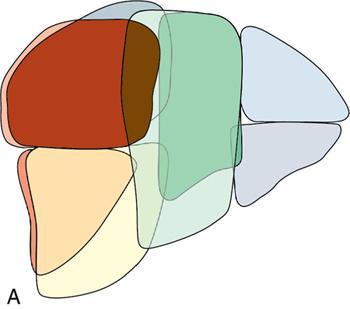

Ritu K. Kashikar, Shrinivas B. Desai Imaging is the mainstay of noninvasive diagnosis of the spectrum of abdominal pathologies or proving absence off thereof. Knowledge of normal anatomy and important normal variants is thus essential for the radiologist in order to avoid misinterpretation or erroneous diagnosis. This chapter highlights the normal anatomy of the hepatobiliary systems including the blood vessel and draining ducts and discusses relevant anatomical variants which may have important clinic implications. The liver is the largest abdominal organ, occupying the right upper abdominal quadrant and is in close approximation with the diaphragm, stomach and the gallbladder. It is largely covered by the costal cartilages. The liver is encapsulated by Glisson’s capsule which is a dense layer of connective tissue. It is covered by peritoneum, except in the regions of gallbladder fossa, fossa for inferior vena cava (IVC), and the bare area. The bare area is the posterocranial aspect of the liver, adjacent to the dorsal body wall, which is not covered by peritoneum. The liver has two surfaces, the convex diaphragmatic surface and a concave visceral surface. The slit in the hepatic hilum is called the porta hepatis and is penetrated by the right and left hepatic ducts (LHDs), hepatic artery and portal vein (PV). The distal portion of the lesser omentum is called the hepatoduodenal ligament and contains the common bile duct (CBD), hepatic artery, PV, nerves of liver and lymphatics. The liver has dual blood supply with hepatic artery providing 25% of hepatic blood and rest by portal vein (Fig. 9.2.1). Five ligaments connect the liver to the undersurface of the diaphragm. These include the falciform, the coronary and two lateral ligaments, all of which are peritoneal folds. The fifth ligament is a fibrous cord-like structure and represents the obliterated umbilical vein. The peritoneum invaginates into the liver parenchyma leading to formation of fissures. There are four normal fissures: fissures for the ligamentum teres, ligamentum venosum and gallbladder and the transverse fissure (Fig. 9.2.2). The liver is organized into microscopic functional units called lobules or acini. A central terminal hepatic venule surrounded by four to six terminal portal triads form a polygonal unit called the hepatic lobule. The terminal portal triad branches line the periphery of the unit. Between the terminal portal triads and the central hepatic venule the hepatocytes are arranged in one cell thick plates, surrounded by sinusoids. The blood flows from the terminal portal triad through sinusoids into terminal hepatic venule. Bile formed within the hepatocytes empties into terminal canaliculi which coalesce into the bile ducts (Fig. 9.2.3). This structure of the functional hepatic unit forms the basis of various functions of the liver. The normal relations of the liver are: The liver can be divided into right, left and caudate lobes. The right and left lobes are separated by the interlobular fissure and is oriented along a line passing through the gallbladder fossa inferiorly and the middle hepatic vein (MHV) superiorly (Fig. 9.2.4). This plane runs from the left of the IVC to the left of the gallbladder fossa and is a called the Cantlie’s line. Use of standardized, segmental anatomy is imperative because it facilitates communication and treatment planning. The segmental anatomy of liver is primarily based on vascular anatomy. The right lobe is divided into anterior and posterior sectors by of the right hepatic vein (RHV). The left lobe is divided into medial and lateraI sectors by an oblique plane connecting the left hepatic vein (LHV) and the falciform ligament. The liver is divided into upper and lower segments at the level of main portal vein (MPV) bifurcation (Fig. 9.2.5). Various systems are used in classification of liver anatomy. These are discussed in Table 9.2.1. The Couinaud’s system is the most commonly used and divides eight sections/segments which are discussed in details below (Table 9.2.2). 1. Segment 1 – Caudate lobe Bounded anteriorly and medially by the fissure for ligamentum venosum (Fig. 9.2.6). 2. Segment 2: Superior segment of the left lateral sector/section Bounded medially by falciform ligament and inferiorly by plane of MPV, also known as the posterior lateral sector (Bismuth, FCAT) (Fig. 9.2.7). 3. Segment 3: Inferior segment of left lateral sector/section Bounded medially by the falciform ligament and superiorly by the plane of the MPV bifurcation, also referred to as lateral anterior sector (Bismuth, FCAT) (Fig. 9.2.8). 4. Segment 4: Left medial sector/section Bounded laterally by falciform ligament and medially by Cantlie’s line (Fig. 9.2.9). 5. Segment 5: Inferior segment of the right anterior sector/section Bounded anteriorly by the gallbladder fossa and posteriorly by the plane of the RHV, superiorly bounded by the plane of MPV bifurcation (Fig. 9.2.10). 6. Segment 6: Inferior segment of the right posterior sector/section Bounded anteriorly by plane of the RHP and superiorly by the plane of the MPV bifurcation (Fig. 9.2.11). 7. Segment 7: Superior segment of the right posterior sector/section Bounded anteriorly by the plane of the RHV and inferiorly by the plane of the MPV bifurcation (Fig. 9.2.12). 8. Segment 8: Superior segment of the right anterior sector/section Bounded anteriorly by the plane of the gallbladder fossa and MHV, posteriorly bounded by the plane of the RHV and inferiorly by the plane of the MPV bifurcation (Fig. 9.2.13). Owing to its broad area of contact with the anterior abdominal wall, the liver is an ideal organ for evaluation with sonography. Ultrasound is commonly used for evaluation of size of the liver. On longitudinal scans obtained through the midhepatic line, if the liver measures 13 cm or less, it is normal in 93% of individuals (Fig. 9.2.14). The size of liver in various planes is discussed in chapter on normograms. When the area of contact between the liver and the anterior border of the right kidney, exceeds below two thirds of the kidney, the liver is considered as enlarged. The normal liver is homogeneous with fine echoes and appears evenly bright. The hepatic veins, PV and fissures interrupt the homogeneity of the liver parenchyma (Fig. 9.2.15). The parenchymal echogenicity may vary depending on the equipment, transducer and gain settings and should be judged by comparison with internal references like right renal cortex, body of the pancreas and PV walls. When compared with the adjacent normal right renal cortex the liver normally appears hyperechoic or isoechoic. The pancreas in a young individual is hypoechoic compared to the liver, and isoechoic in middle aged adults. As age progresses and fatty infiltration of the pancreas occurs, the pancreas appears hyperechoic to the liver. The liver is hypoechoic to the spleen. The normal liver reveals a density of 55–65 HU on nonenhanced scan and should appear homogenous with the exception of hypodensity in the regions of vessels and fissures. The liver parenchymal enhancement is minimal the arterial phase, with increase in density by only approximately 10 HU. This phase is usually to access vascular anatomy and to detect neovascular enhancing lesion like HCC, metastasis. Considering the fact that 75% of heptic venous supply is from the PV, the normal hepatic parenchyma shows maximum enhancement in the portal venous phase. During the venous/delayed phase the hepatic attenuation starts falling (Fig. 9.2.16). The hepatic fissures appear as linear fat containing structures. All the four fissures are well identifies on CT (Figs. 9.2.17–9.2.20). Normal liver should demonstrate uniform T1 signal similar or isointense to the paraspinal muscles and slightly hyper intense to the spleen. No signal drop should be seen on in or opposite phase. On T2W1 images liver appears slightly hyperintense to paraspinal muscles, isointense to pancreas and hypointense to spleen (Fig. 9.2.21). Following administration of extracellular contrast agents the normal liver parenchyma enhances on PV phase similar to that seen on CT. The arterial phase is preserved to determining vascular anatomy, variants and tumoural enhancement. Gadoxetic acid (Eovist) and gadobenate dimeglumine (MultiHance) are hepatobiliary agents showing excretion by the liver. In the case of gadoxetic acid, hepatic excretion is ~50%, which allows imaging in the hepatobiliary phase at ~20 minutes following injection. Gadobenate has only 3%–5% biliary excretion with hepatobiliary phase at approximately 40 minutes (Fig. 9.2.22). This property makes these agents useful in detection of nonhepatocyte containing lesions which appear hypointense to background liver on hepatobiliary phase. Hepatic anatomic variants are relatively common and represent normal interindividual variation of liver morphology. Normal Anatomic Variants Anatomic anomalies Accessory and pseudofissures may be seen in the liver. True accessory fissures result from infolding of the peritoneum usually along the undersurface of the liver and are rare. The inferior accessory fissure is the commonest accessory fissure and divides the posterior segment of the right hepatic lobe into lateral and medial portions. Diaphragmatic slips may cause indentation over the liver surface and are not commonly seen on imaging (Fig. 9.2.23). Leftward extension of the lateral segment of the left hepatic lobe appearing as a crescentic density that wraps around the spleen is referred to as sliver of liver. The left lobe of the liver may exhibit various forms: leaf like; spatular; truncated pyramid/wedge shaped; and a bifid appearance (Fig. 9.2.24). Elongated left lobe may be mimic splenomegaly, perisplenic hypoechoic collections or less commonly tumours. Imaging clues to diagnosis are establishing contiguity with liver and visualization of parenchymal vessels coursing through. The portion of the liver that extends medially from the right lobe between the IVC and fissure for ligamentum venosum is called the caudate lobe. The caudate lobe is divided inferiorly into a lateral caudate process and a medial papillary process. The medial papillary process projects medially towards the pancreatic head and has applied importance (Fig. 9.2.25). Riedel’s lobe is a tongue-like projection from the anterior aspect of the right lobe and the most common accessory lobe of the liver. It is seen most frequently in asthenic women. The reported prevalence of RL, ranges from 3.3% to 14.5% and the prevalence is higher in women than in men. It can be 20 cm or more in length and may extend up to the iliac fossa. It is usually asymptomatic and is discovered incidentally (Fig. 9.2.26). Accessory liver lobes are defined as a supernumerary lobe of normal hepatic parenchyma in continuity with the liver. This is a rare entity and usually occurs as a result of congenital ectopic hepatic tissue, although rarely may occur as a result of trauma or surgery. Various systems are proposed for classification of ALL. Another method of classification has been proposed based on biliary drainage and presence or absence of capsule. Accessory lobes can be readily diagnosed and characterized on CT or magnetic resonance imaging (MRI) done for related or unrelated conditions. CT shows the lesion as a soft–tissue density mass attached to the liver and isodense to the organ. The portal/hepatic venous branches can be seen coursing through it, in contiguity with the liver (Fig. 9.2.27). The coeliac axis trifurcates into common hepatic, splenic and left gastric arteries at the level of T12–L1. The common hepatic artery becomes the proper hepatic artery after origin of the gastro-duodenal artery. The hepatic artery proper ascends anterior to the PV and medial to the CBD and divides in to right and left hepatic artery (LHA). Occasionally the middle hepatic (segment 4) artery arises from hepatic artery proper. The hepatic artery appears as a tubular hypoechoic structure and shows antegrade flow on Doppler (Fig. 9.2.28). Normally the resistive index is low ranging between 0.55 and 0.7. The hepatic artery, its anatomy, branches, course, calibre are best evaluated on arterial phase of dynamic CT (Fig. 9.2.29). This is also the preferred modality prior to hepatobiliary surgical planning. Contrast-enhanced MRI also shows the above details but spatial resolution is lower. Road map of the arterial vascularity of the donor and recipient is a prerequisite for transplant surgery and complex hepatobiliary surgery. Detailed hepatic arterial anatomy and its variations have its significance in liver surgeries and interventional hepatic procedures, relative to the hepatic lobe involved. A classification method was described by Michel et al. in 1955, and is discussed in Table 9.2.3 (Fig. 9.2.30). I: standard anatomy ~60% (range 55%–61%) II: replaced LHA ∼7.5% (range 3%–10%) III: replaced RHA ~10% (range 8%–11 %) IV: replaced RHA and LHA ~1% V: accessory LHA from LGA ~10% (range 8%–11%) VI: accessory RHA from SMA ~5% (range 1.5%–7%) VII: accessory RHA and LHA ~1% VIII: accessory RHA and LHA and replaced LHA or RHA ~2.5% IX: CHA replaced to SMA ~3% (range 2%–4.5%) X: CHA replaced to LGA ~0.5% Other unclassified variants are: The two most common variants are the replaced right hepatic artery (RHA) arising from the SMA (Fig. 9.2.31) and replaced LHA arising from the left gastric artery (Figs. 9.2.32–9.2.34). Segment 4 artery – Middle hepatic artery (MHA) The middle hepatic artery usually arises from the LHA, it may, however, arise from the RHA (Fig. 9.2.35). The knowledge regarding origin of MHA is imperative in transplant surgery. The MHA can arise from RHA in Patients with replaced LHA. In patients with replaced RHA, the MHA arises from LHA (Fig. 9.2.36). Because of the considerable variability of hepatic arterial anatomy, assessment of this anatomy is crucial in the preoperative evaluation of potential living liver donors. Relevance of donor and recipient arterial anatomy is discussed in details in chapter on liver transplant. The relationship between the arterial variant and tumour is important to establish prior to major surgeries. Injuries to aberrant hepatic vessels and secondary ischaemic biliary strictures can be avoided. A replaced RHA has a more posterior course and long length. This variant may be advantageous in patients undergoing right lobar resection. However, there is greater propensity of involvement of replaced RHA by pancreatic head. The radiologist must be vigilant in reporting this variant (Fig. 9.2.37). Accessory RHA can, however, be sacrificed even if encased by neoplasm. An accessory LHA needs to be ligated separately in surgeries where blood supply in the porta hepatis is occluded. Replaced LHA from LGA maybe injured in case of surgeries at the level of hiatus. Hence this variant should be informed to surgeon in patients undergoing gastric surgeries. Preoperative mapping of the hepatic arterial anatomy prior to placement of intraarterial chemotherapy pumps is essential because it helps in deciding whether the candidate is suitable for the procedure and also if technical modifications are needed. The intraarterial infusion pump should be placed in the dominant hepatic artery as proximal as possible, but beyond GDA origin. Inpatients with standard anatomy, the pump is usually placed in the hepatic artery prior just after GDA origin. The location of pump can be modified in patients with variant anatomy, based on origin of GDA and dominant hepatic vessel. The PV is the main vessel in the portal venous system and drains blood from the gastrointestinal tract and spleen to the liver.